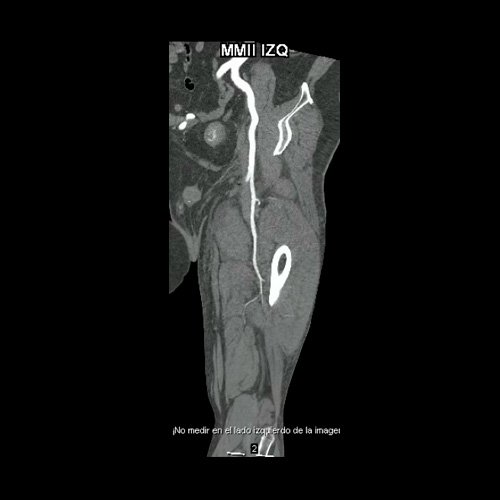

• Flebotomografia de miembros inferiores (Día 18): Filtro de vena cava inferior infrayacente a venas renales. Stent metálico a nivel de la vena ilíaca común y externa izquierda, permeable. Se explora la región venosa del territorio femoral y poplíteo, evidenciándose defectos parciales de relleno endoluminal a nivel de la vena femoral superficial y profunda izquierdas, compatibles con trombosis venosa parcial. A nivel del tercio distal de la vena femoral común izquierda, se evidencia aumento de calibre e interrupción brusca de la opacificación del contraste (“signo de stop”), compatible con trombosis venosa oclusiva en dicho nivel, sin opacificación venosa distal. Se observan similares hallazgos a nivel de la vena femoral superficial contralateral, evidenciándose defectos de relleno endoluminal parcial hasta su tercio distal, con ausencia de opacificación distal. Salvo mejor criterio sugiero complementar con eco-Doppler de venoso de ambos miembros inferiores. Presenta edema difuso de los tejidos blandos de miembro inferior izquierdo. Se observa en los tejidos blandos de la región inguinal izquierda, colección hipodensa con realce periférico que mide 4.7 cm AP x 4 cm. Además se observan ganglios locorregionales aumentados en número y tamaño, algunos de rango megálico.

Flebotomografia de miembros inferiores (Día 18)